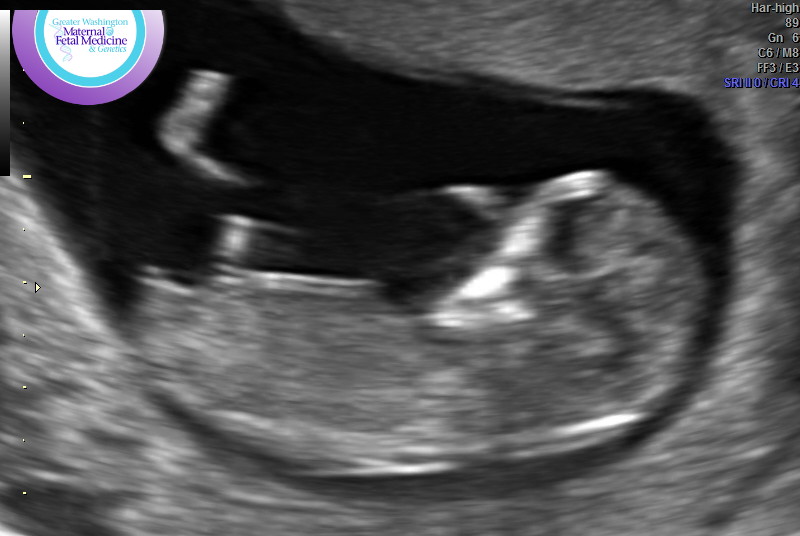

Here are the nub/skull pics again:

Attachment 41115Attachment 41116Attachment 41117Attachment 41118Attachment 41119